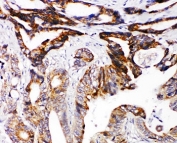

IHC-P: DCC antibody testing of human intestinal cancer tissue.